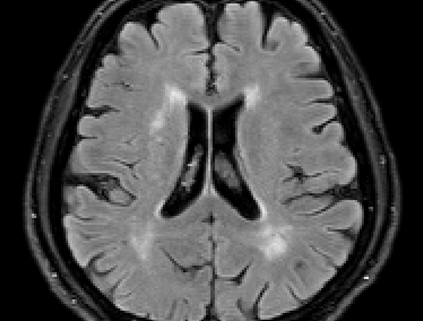

Brain atrophy and white matter hyperintensity (WMH) are critical neuroimaging features for ascertaining brain injury in cerebrovascular disease and multiple sclerosis. Automated segmentation and quantification is desirable but existing methods require high-resolution MRI with good signal-to-noise ratio (SNR). This precludes application to clinical and low-field portable MRI (pMRI) scans, thus hampering large-scale tracking of atrophy and WMH progression, especially in underserved areas where pMRI has huge potential. Here we present a method that segments white matter hyperintensity and 36 brain regions from scans of any resolution and contrast (including pMRI) without retraining. We show results on six public datasets and on a private dataset with paired high- and low-field scans (3T and 64mT), where we attain strong correlation between the WMH ($\rho$=.85) and hippocampal volumes (r=.89) estimated at both fields. Our method is publicly available as part of FreeSurfer, at: http://surfer.nmr.mgh.harvard.edu/fswiki/WMH-SynthSeg.